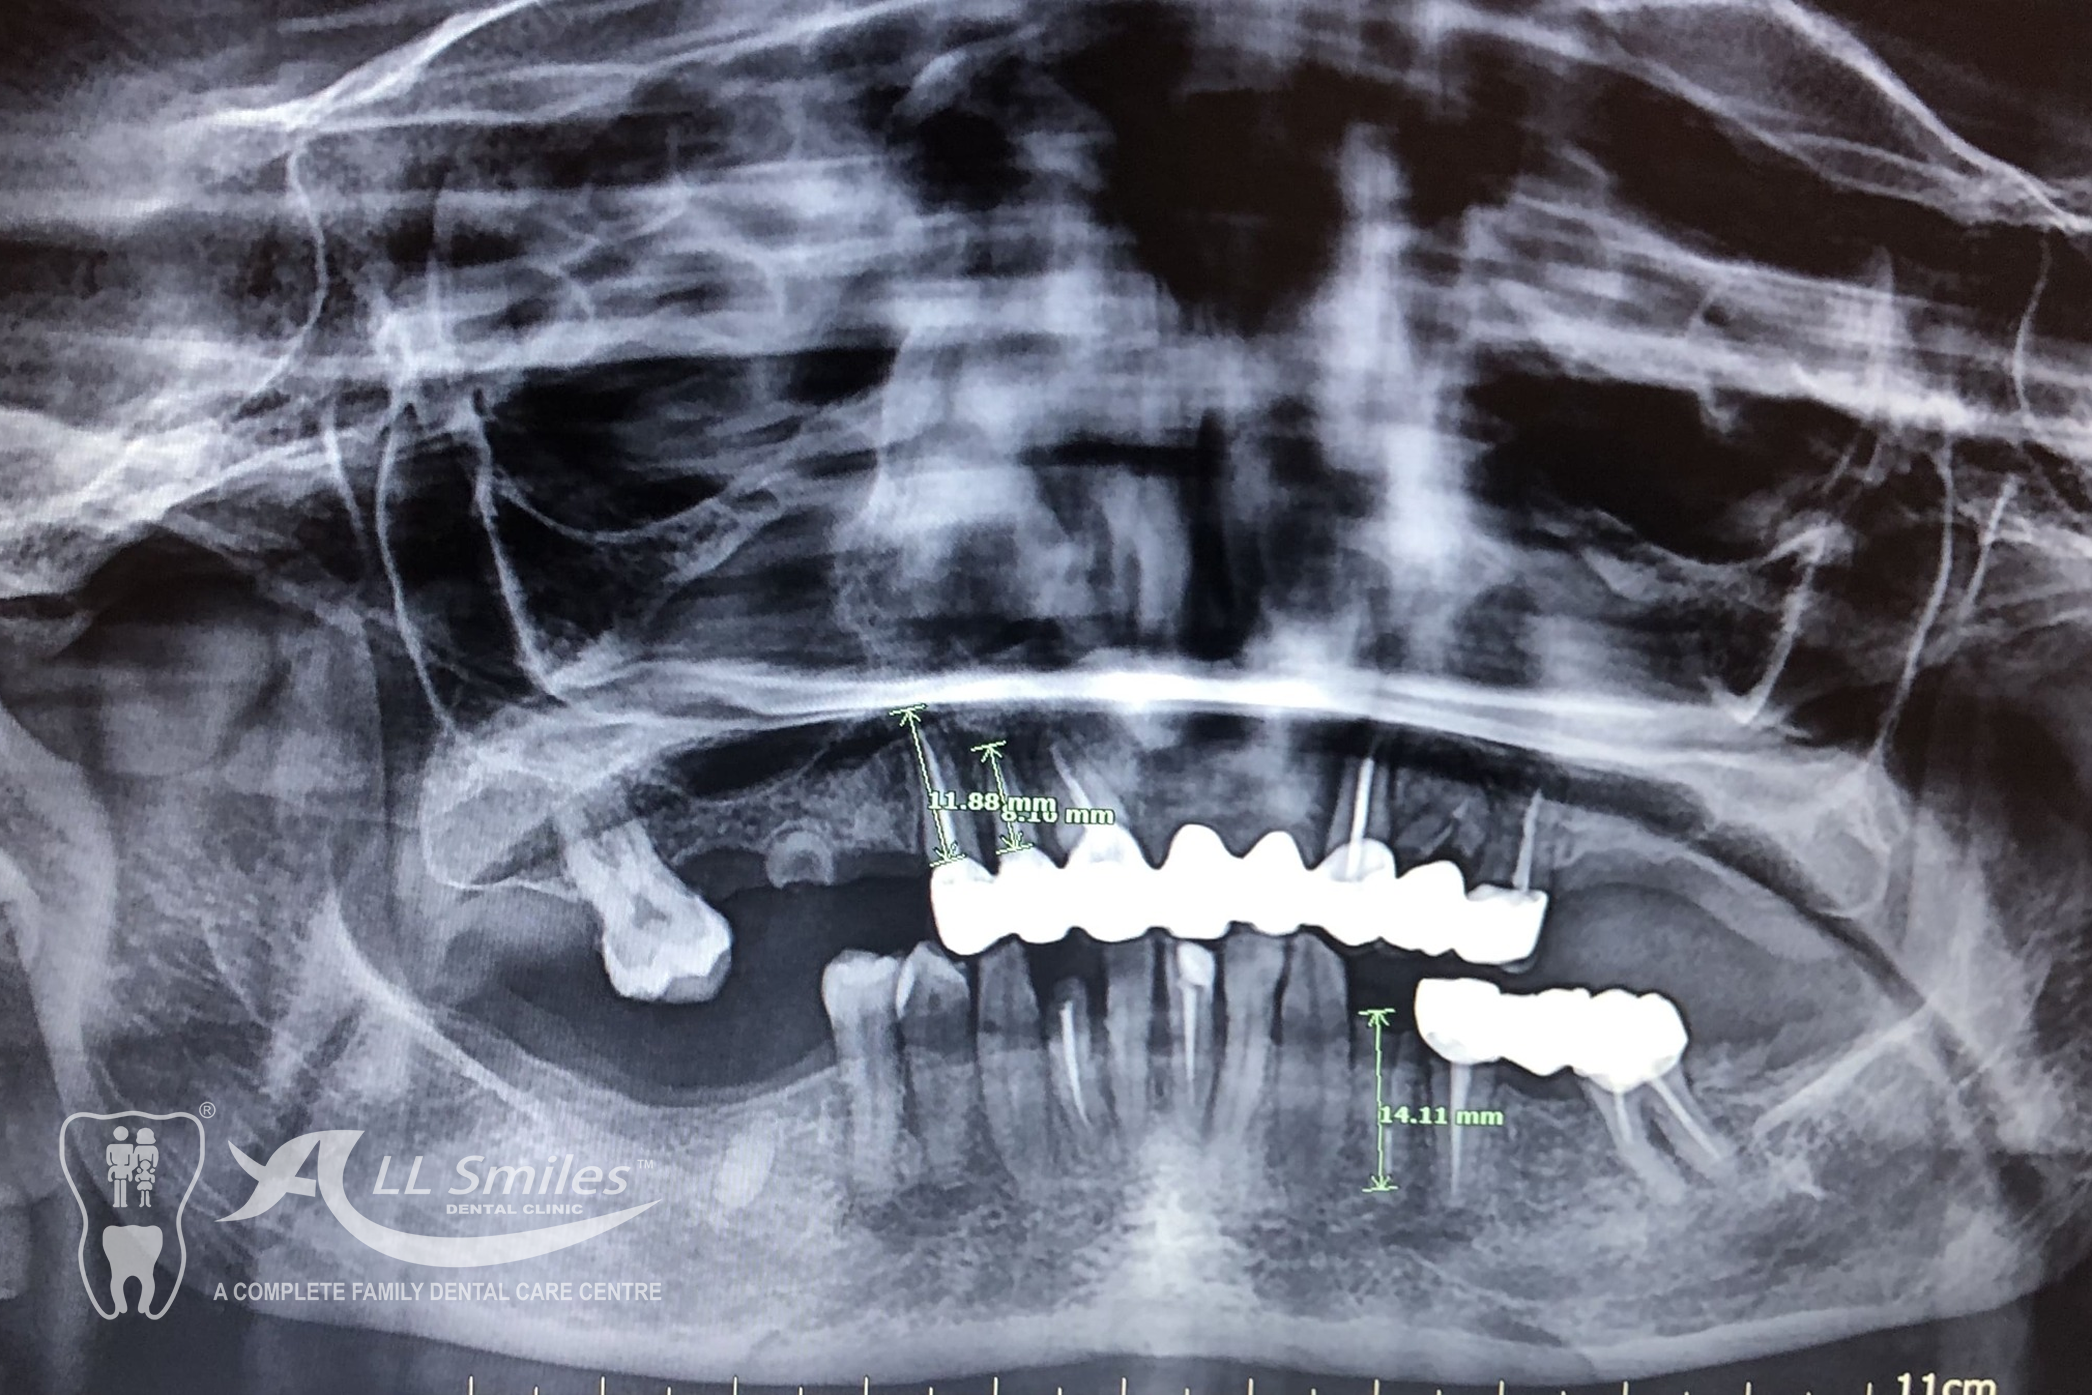

After precise planning the new tooth roots are generally placed in the jaw in one single treatment session. A temporary denture closes the gaps during the healing phase. After healing the final crowns or the bridge are permanently fixed to the implants. Life With Bite! Dental Implants For The Edentulous Jaw.

- All on 4 or All on 6: A bridge can be permanently anchored to 4 or 6 implants in your jaw. The Implants for each arch are placed in a single appointment. It is often possible to fix the provisional denture to the new roots at the same time implants are placed in the jaw. You come to the appointment in the practice and leave few hours later with firmly fixed, beautiful teeth. After the healing phase this is replaced by the permanent ceramic or acrylic prosthesis.

A bridge can be permanently anchored to 4 or 6 implants in your jaw. The Implants for each arch are placed in a single appointment. It is often possible to fix the provisional denture to the new roots at the same time implants are placed in the jaw. You come to the appointment in the practice and leave few hours later with firmly fixed, beautiful teeth. After the healing phase this is replaced by the permanent ceramic or acrylic prosthesis.